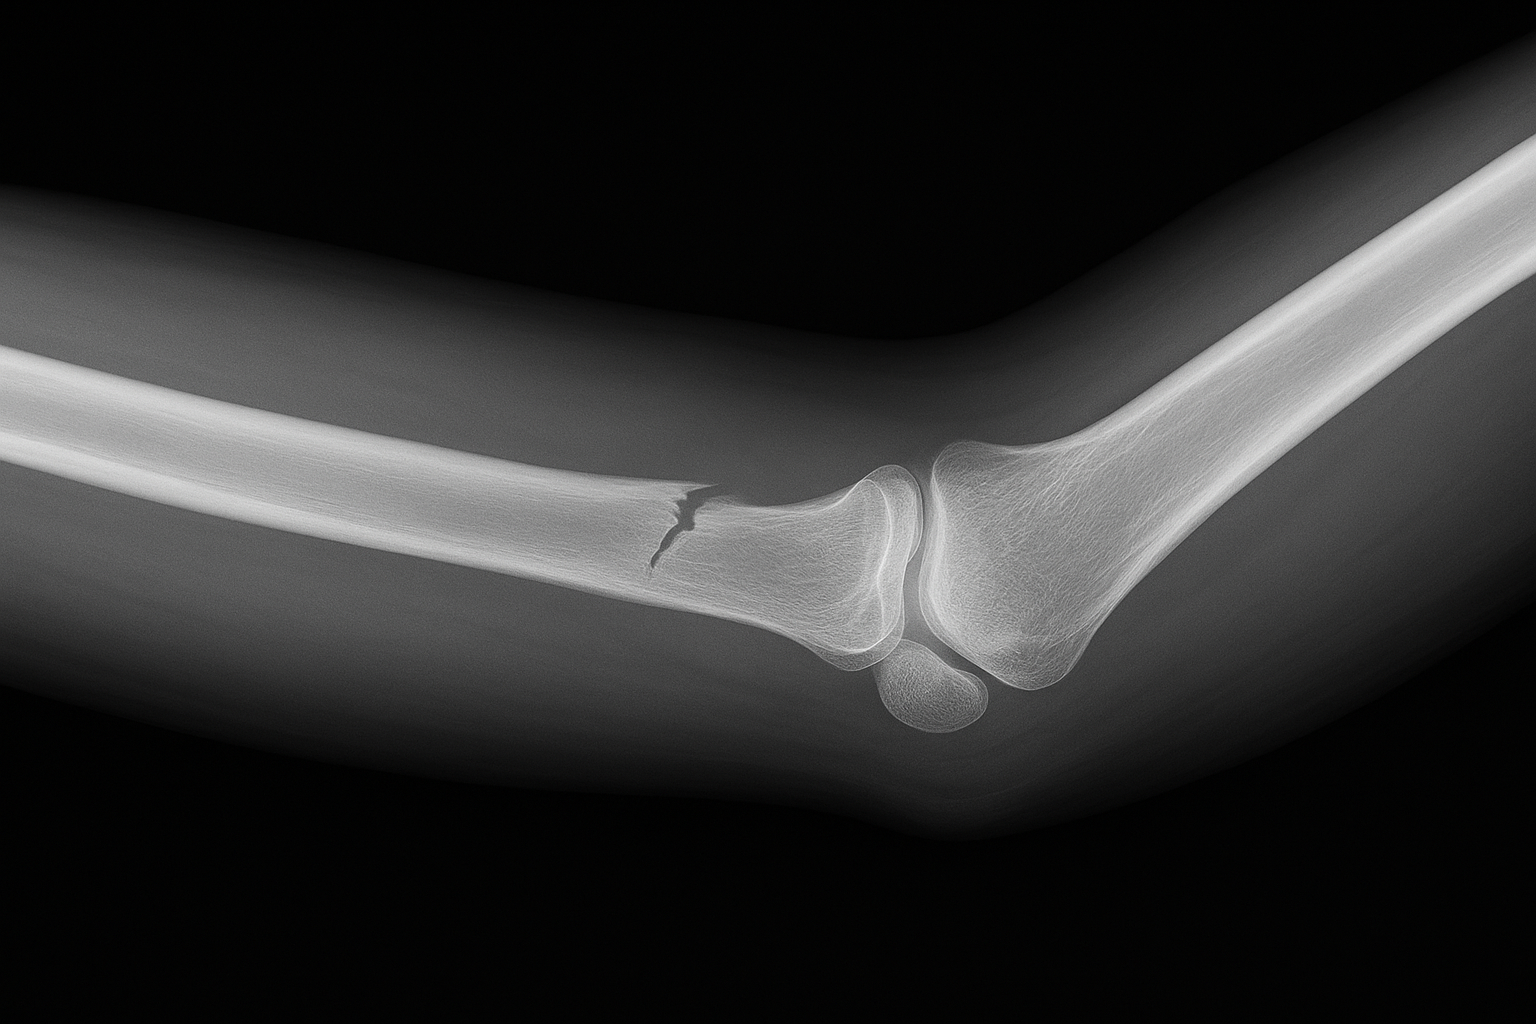

「骨にひびが入った」という表現は、医学的には不全骨折や亀裂骨折と呼ばれる状態を指すことが多いと言われています。これは骨が完全に折れているわけではなく、部分的に損傷している状態です(引用元:リハサク)。レントゲン写真でかすかな線状の損傷が確認されることもあり、日常生活に支障をきたす痛みや腫れを伴うケースがあります。

不全骨折は、骨の連続性が保たれつつも一部にヒビが入った状態とされ、外力の大きさや方向によって症状の出方が異なると言われています(引用元:メディカルコンサルティング)。一方で、亀裂骨折は骨の表面に走る細い割れ目が特徴で、強い衝撃や繰り返しの負荷で起こることが多いとされています。

骨にひびが入った疑いがある場合、まず行われるのは画像検査です。一般的にはレントゲン撮影で骨の状態を確認しますが、不全骨折や亀裂骨折は画像に映りにくい場合があると言われています(引用元:倉石整形外科クリニック、リハサク)。そのようなケースでは、CTスキャンで詳細な骨の断面を確認したり、MRIで骨周囲の軟部組織や骨髄の変化を捉える方法が有効とされています。特に早期段階での小さな損傷は、MRIのほうが発見しやすいこともあると言われています。